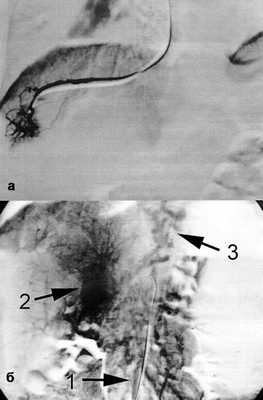

Больная оперирована в объеме Н-образного аутовенозного мезоренального шунтирования трансплантатом из левой внутренней яремной вены. В условиях эпидуральной анестезии с ИВЛ выполнена бисубкостальная лапаротомия. Разделены множественные сращения в верхнем отделе брюшной полости. Асцита нет, печень обычного цвета, не увеличена в размерах, поверхность гладкая, край острый, вены желудка, большого сальника, брыжейки тонкой кишки расширены. Других патологических изменений не выявлено. Из окружающих тканей выделен и мобилизован на протяжении 4 см левый приток верхней брыжеечной вены диаметром 6 мм под перешейком поджелудочной железы. Основной ствол вены постфлебитически изменен и втянут в рубец в проекции инфраренального отдела нижней полой вены. Мобилизован нижнегоризонтальный отдел двенадцатиперстной кишки. Выделена и мобилизована на протяжении 4 см антеаортально расположенная левая почечная вена. Линейным разрезом по медиальному краю кивательной мышцы слева выделена левая внутренняя яремная вена диаметром 6 мм, фрагмент длиной 4 см забран для использования в качестве трансплантата, центральная и дистальная культи яремной вены ушиты. Выполнено боковое отжатие левой почечной вены зажимом Сатинского, приток верхней брыжеечной вены выключен из кровотока клампами Де Бейки. Последовательно сформированы анастомозы аутовенозного трансплантата в изогемодинамической позиции с левой почечной и верхней брыжеечной венами нитью пролен 6/0 growth factor (рис. 3). Рисунок 3. Вид сформированного Н-образного мезоренального шунта. 1 - левый приток верхней брыжеечной вены; 2 - левая почечная вена; 3 - восходящий отдел двенадцатиперстной кишки. Сняты зажимы с вен. Портосистемный градиент до пуска кровотока составил 20 мм рт.ст., после пуска кровотока снизился до 7 мм рт.ст. Взят биопсийный материал из края III сегмента печени, при гистологическом исследовании данных, свидетельствующих о циррозе и активном гепатите, нет.

Больная экстубирована через 3 ч при нормальных показателях газообмена и гемодинамики. Послеоперационный период протекал без осложнений, пациентка выписана в удовлетворительном состоянии через 10 сут после операции без признаков постшунтовой энцефалопатии. Перед выпиской выполнена контрольная эзофагогастродуоденоскопия, при которой отмечена полная редукция варикозно-расширенных вен пищевода и желудка (см. рис. 1, б). Через месяц после выписки выполнена МСКТ-ангиография, при которой визуализирован проходимый мезоренальный шунт (рис. 4). Рисунок 4. Мультиспиральная компьютерная томограмма после операции. 1 - левый приток верхней брыжеечной вены; 2 - левая почечная вена.

Больная Р., 49 лет, госпитализирована в Государственную новосибирскую областную клиническую больницу в связи с выявленным асимптомным варикозным расширением вен пищевода. За год до поступления при скрининговом ультразвуковом исследовании было обнаружено гиперваскулярное образование в области ворот печени, а при последующей компьютерной томографии в другом стационаре в области ворот печени визуализировано мягкотканное образование с нечеткими контурами размером 5×5×4 см (рис. 1, а), Рисунок 1. Спиральная компьютерная томограмма до (а) и после (б) мезентерико-кавального шунтирования. 1 - портальная кавернома, первоначально принятая за опухоль ворот печени; 2 - верхняя брыжеечная вена; 3 - нижняя полая вена, 4 - мезентерико-кавальный анастомоз. расцененное как опухоль ворот печени. При этом больная не предъявляла каких-либо жалоб, не было изменений в биохимическом анализе крови, гемограмме и отсутствовали характерные для опухолей данной локализации проявления механической желтухи. Месяцем позже в другом лечебном учреждении была выполнена лапароскопия, во время которой не найдено признаков неопластического процесса в брюшной полости, но обращено внимание на наличие спленомегалии и множества расширенных вен в области малого сальника и брыжейки тонкой кишки. Тогда же была произведена биопсия печени, а после гистологического исследования получено заключение о формирующемся микронодулярном циррозе. В течение 11 мес пациентка наблюдалась и лечилась в различных гастроэнтерологических отделениях с диагнозом криптогенного цирроза печени, во время последней госпитализации эндоскопически было выявлено варикозное расширение вен пищевода.

При эзофагогастродуоденоскопии перед выпиской отмечена хорошая редукция варикозно-расширенных вен пищевода (рис. 2, б), при компьютерной томографии через 1 мес после выписки визуализирован проходимый мезентерико-кавальный анастомоз (рис. 1, б). Во время контрольного осмотра через 3 мес состояние пациентки удовлетворительное, принимает кардиомагнил по 75 мг/сут, доза гидроксикарбамида снижена до 1000 мг/сут. Показатели гемограммы: Hb 107 г/л, эр. 5,04·10 12 /л, л. 9,6·10 9 /л, Ht 32,9%, тр. 505·10 9 /л, средний объем эритроцитов 65 фл, среднее содержание гемоглобина в эритроците 21,3 пг, лейкоцитарная формула не изменена.